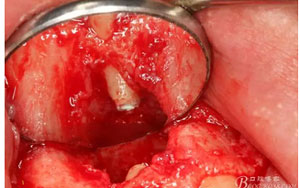

圖1.患者在根管術(shù)前的根尖片影像檢查:12有開髓孔,根尖有橢圓形陰影。

圖9.翻開角形瓣后,有骨壁缺損,囊壁有穿孔,這就是溢膿的竇道出口。

圖13.囊壁摘除后形成的骨腔,12牙根完全裸露在骨腔內(nèi)。